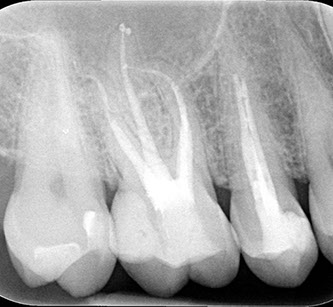

• controllo radiografico

All'esame radiografico, sia l'Ascesso che il Granuloma sono rappresentati da  un'area di ridotta densità ossea, visibile come un'areola scura in prossimità dell'apice radicolare.